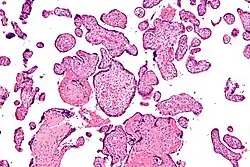

![]() Micrografía de vilitis de etiología desconocida. Tinción H&E. | ||

La VUE puede ser de 2 tipos, villitis crónica de bajo grado o villitis crónica de alto grado. La vellosidad crónica de bajo grado involucra menos de 10 vellosidades que contienen linfocitos. La vilitis crónica de bajo grado puede ser focal o multifocal. Focal ha involucrado vellosidades en solo un portaobjetos de vidrio, mientras que multifocal ha involucrado vellosidades en al menos dos portaobjetos. La vellosidad crónica de alto grado tiene más de 10 vellosidades inflamadas por foco. La villitis crónica de alto grado se diferencia en difusa y parcheada. El término parcheado se usa si menos del 30% de las vellosidades distales están involucradas. El término difusa se utiliza si más del 30% de las vellosidades distales están involucradas.

La VUE tiene 2 patrones distintos prominentes. Aproximadamente el 50% de los casos únicamente involucran las vellosidades distales (vellosidades intermedias y terminales maduras) y no involucran las vellosidades del tallo proximal, las vellosidades de anclaje incrustadas en la placa basal y la placa coriónica. El segundo patrón más común (aproximadamente el 30% de los casos de VUE) involucra las vellosidades del tallo proximal (y posiblemente la placa coriónica) y, por lo general, las vellosidades distales. Este tipo de VUE está relacionado con lesiones obstructivas vasculares fetales (vasculopatía fetal obliterante).[1][15]

Histomorfológicamente, la VUE se caracteriza por un infiltrado linfocitario de las vellosidades coriónicas sin una causa demostrable. Las células plasmáticas deben estar ausentes; la presencia de células plasmáticas sugiere una etiología infecciosa, por ejemplo, infección por CMV.